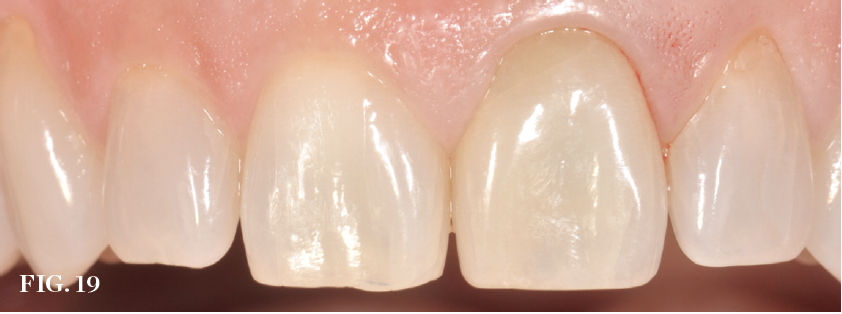

(19.) Preoperative view of a failing central incisor (tooth No. 9). Note the early recession occurring in the region.

Figure 19

(20.) Immediate implant placement. The residual bone defect, which measures approxi-mately 3 mm, was intentionally developed by planning the use of a suitable implant diameter.

Figure 20

(21.) Guided bone regeneration using a collagen membrane and adapted bone graft.

Figure 21

(22.) Prefabricated custom healing abutment. Note the facial cutback to allow for the addition of a connective tissue graft to level the gingival margin with the contralateral dentition.

Figure 22

Guided Bone Regeneration

Management of the defect between the implant and socket walls and contour enhancement beyond the facial/buccal socket wall are almost always required in immediate placement approaches. Bone grafting of the residual horizontal defect and, at times, buccal contour augmentation are used to compensate for expected buccal plate changes resulting from extraction, especially when the bone morphotype is thin (Figure 19 through Figure 22). Soft-tissue grafts can be used to further support stable facial tissues, but they will not completely prevent changes in bone volume that are associated with postextraction remodeling (Figure 23 and Figure 24).